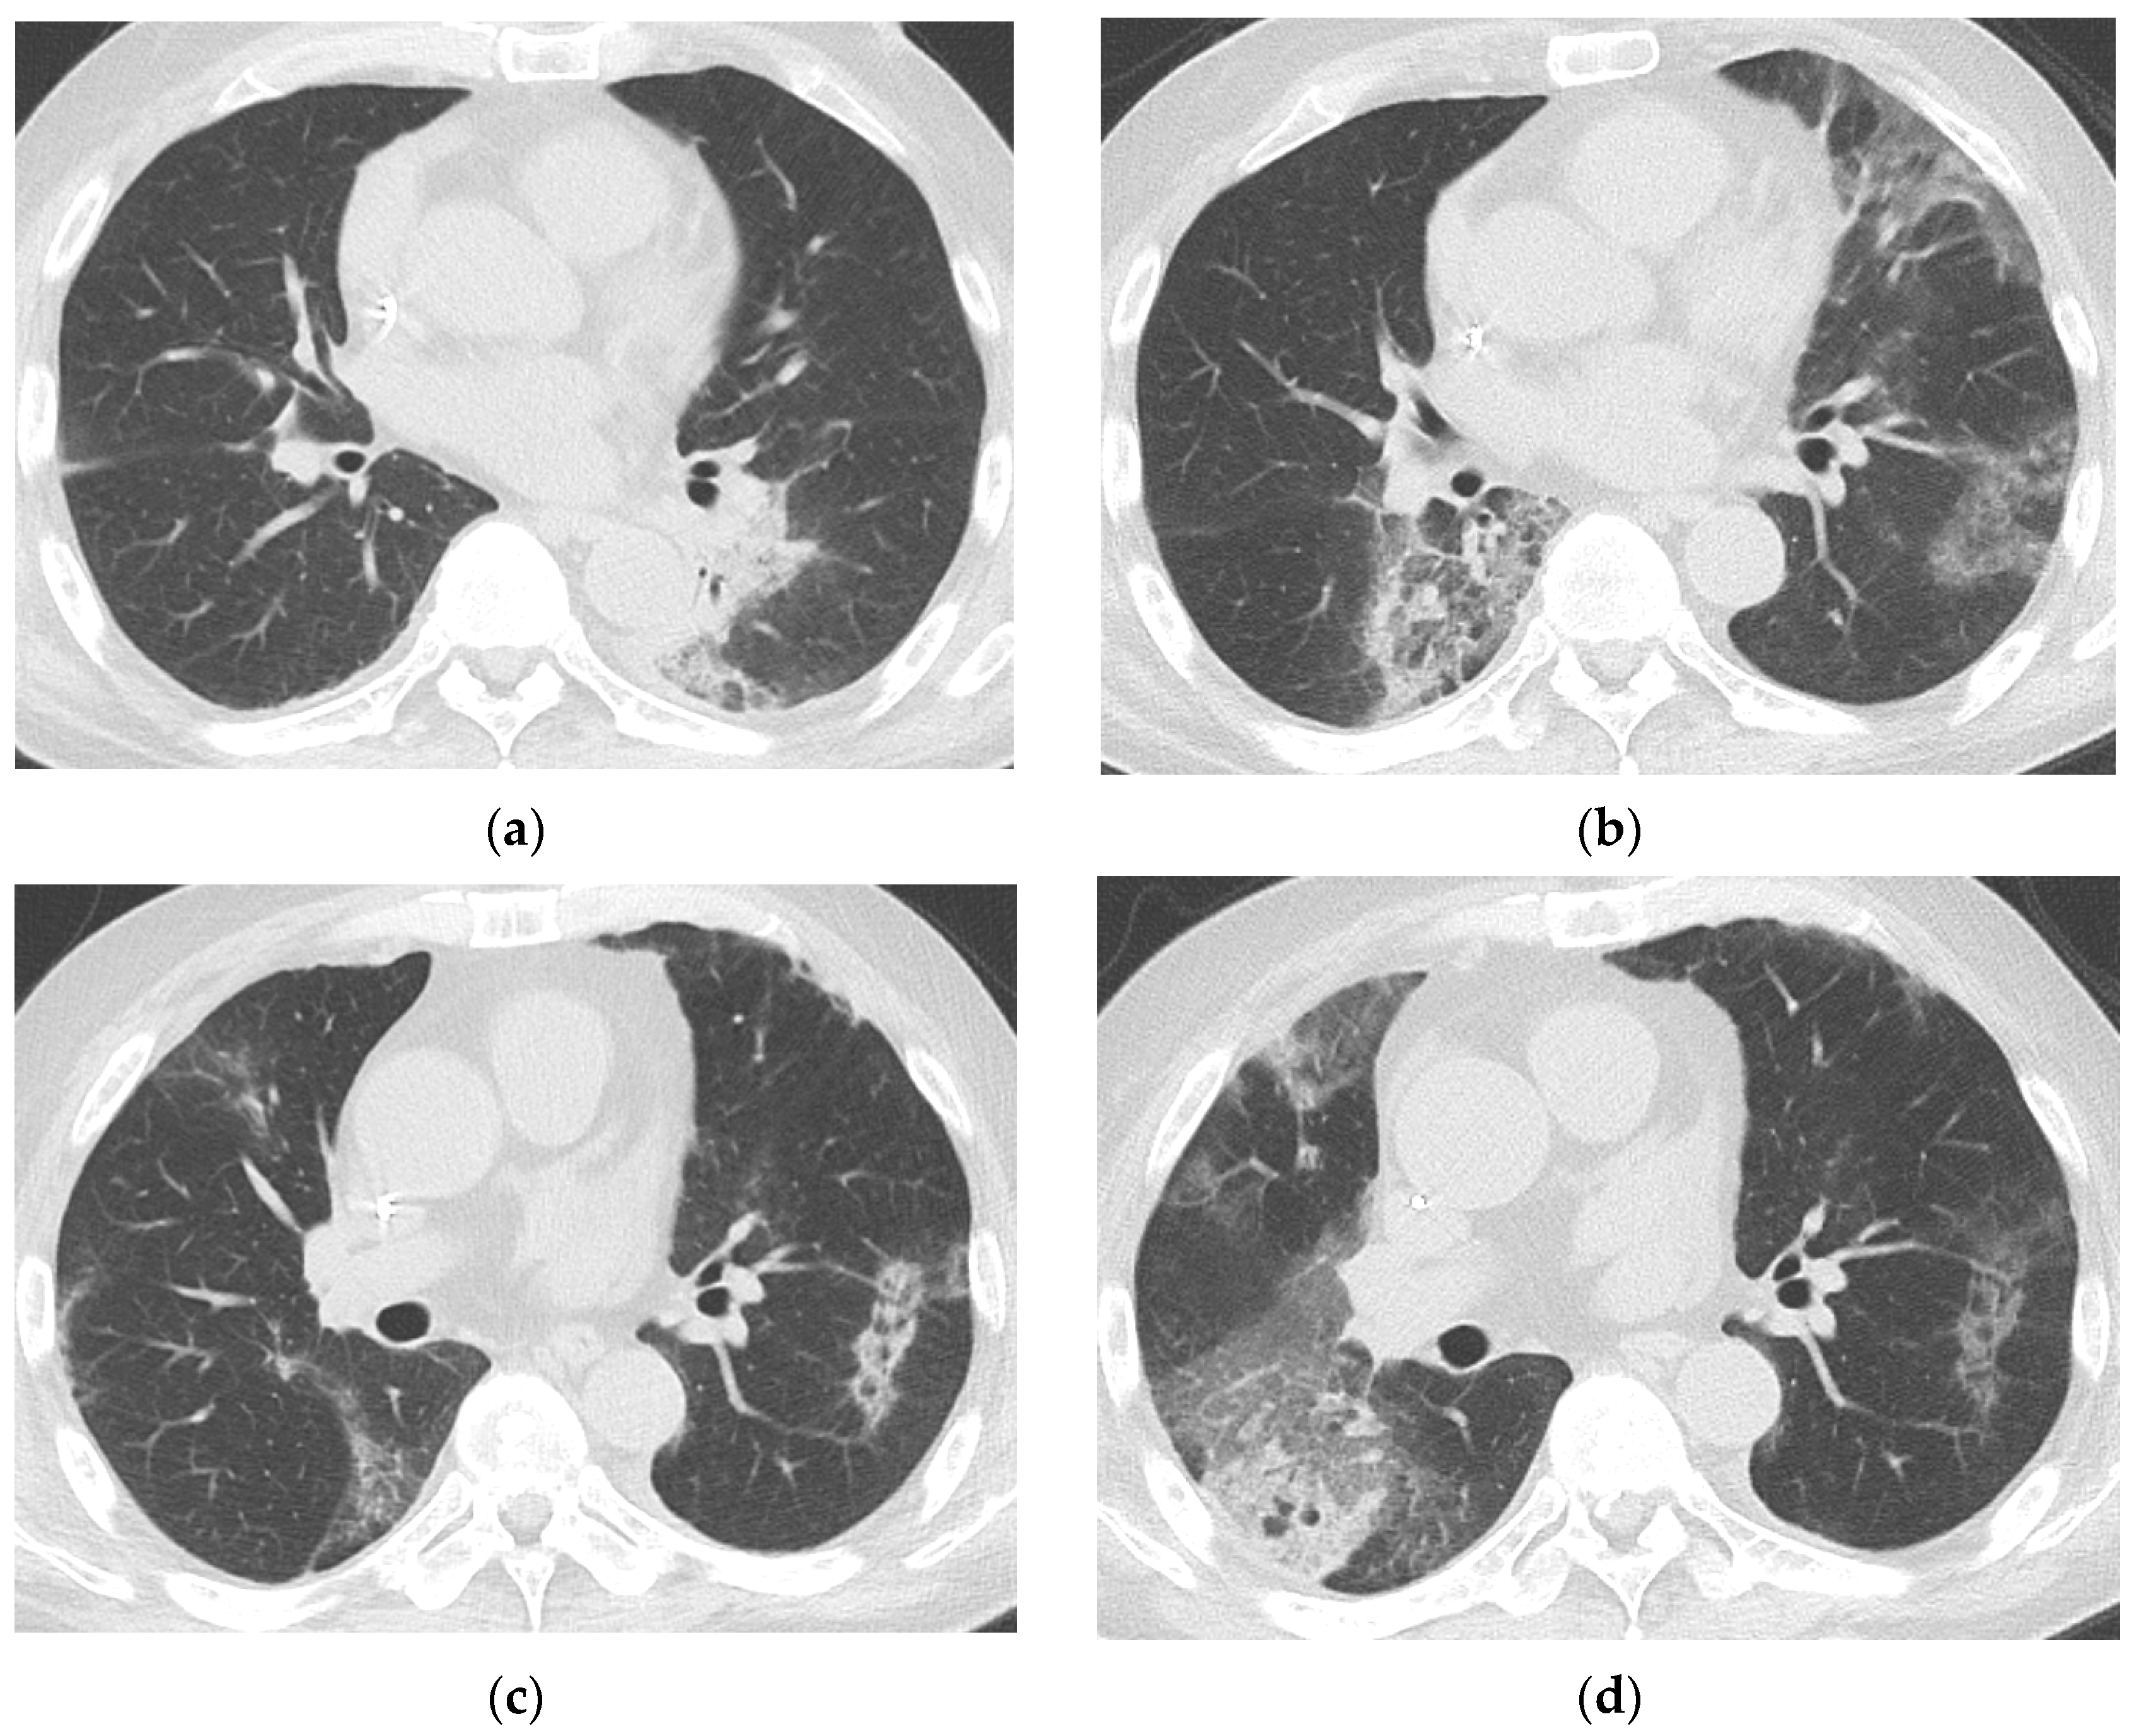

3.3. Baseline and Follow-Up Chest CT Findings

4. Discussion